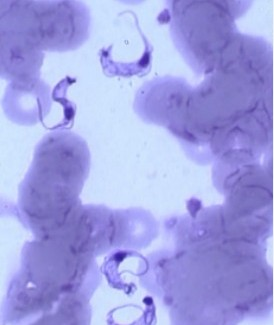

31.有關感染巴貝西亞原蟲(Babesia spp.)患者的血液抹片檢查,下列何者正確?

(C)蟲體為戒指型(ring forms)

樓上是錐形蟲的圖吧 可是這題是問巴貝西...